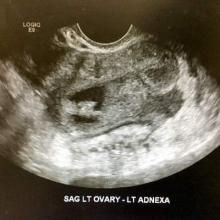

Ultrasound view of an endometrioma with a mural nodule. Courtesy of Dr. Farr Nezhat

Ultrasound view of an endometrioma with a mural nodule.